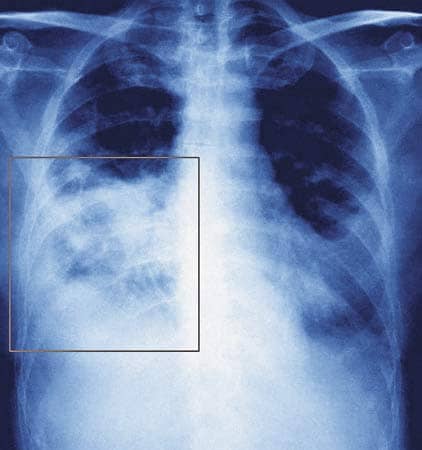

Одним из опасных осложнений при свином гриппе является развитие пневмонии. Воспаление легких может явиться следствием воздействия вируса гриппа (первичная; может быть связана с присоединением вторичной бактериальной флоры (вторичная); может быть следствием действия и вируса и сопутствующего наслоения бактериальной флоры (смешанная).

Первичная пневмония развивается на вторые-третьи сутки от начала заболевания и характеризуется развитием симптомов острой дыхательной недостаточности: больной часто дышит (около 40 дыханий в минуту при норме - 16), в акте дыхания активно участвуют вспомогательные мышцы (диафрагма, мышцы живота), выраженный сухой или малопродуктивный кашель (отделяемое слизистое и прозрачное), выраженная одышка, посинение кожных покровов (цианоз). При выслушивании легких: влажные хрипы в нижних отделах легких преимущественно на высоте вдоха, притупление перкуторного звука при простукивании легких.

Нередко первичные пневмонии приводят к образованию респираторного дистресс-синдрома (развитие отека легкого) с возможным смертельным исходом.

Вторичная пневмония возникает на 6-10 день от начала заболевания. Чаще всего имеет место пневмококковая обсемененность (у 45% больных), реже золотистый стафилококк (не более 18%), а также гемофильная палочка. Особенностью данной пневмонии будет усиление кашля: он становится мучительным, практически постоянным, на фоне усиления кашля у больного вторая волна лихорадки и интоксикации, пациент практически не принимает пищу. Нарастает боль в грудной клетке при кашле и даже дыхании. Отделяемое легких (мокрота) уже не прозрачное, а имеет гнойный оттенок. При рентгенографии – очаги воспаления в легких. Течение вторичной пневмонии продолжительное, больные не могут поправиться месяц-полтора. Нередко стафилококковые пневмонии приводят к образованию абсцесса легких.

Пневмония при свином гриппе

Смешанные пневмонии имеют клинические симптомы и одной, и второй пневмонии, протекают длительно (проградиентно), трудно поддаются лечению.